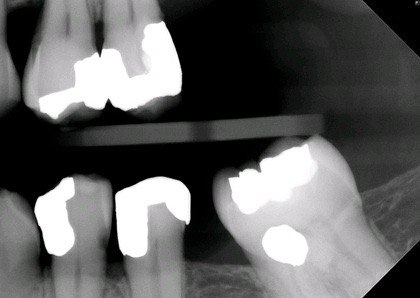

6. What is the condition on dista surface of the tooth # 3.7?

16. What condition can be seen in distal of tooth # 3.7?

19. What is the condition on the distal surface of the tooth # 3.7?

24. What condition can be seen on the distal surface of the tooth # 3.7?